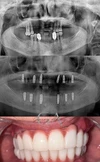

زراعة الأسنان